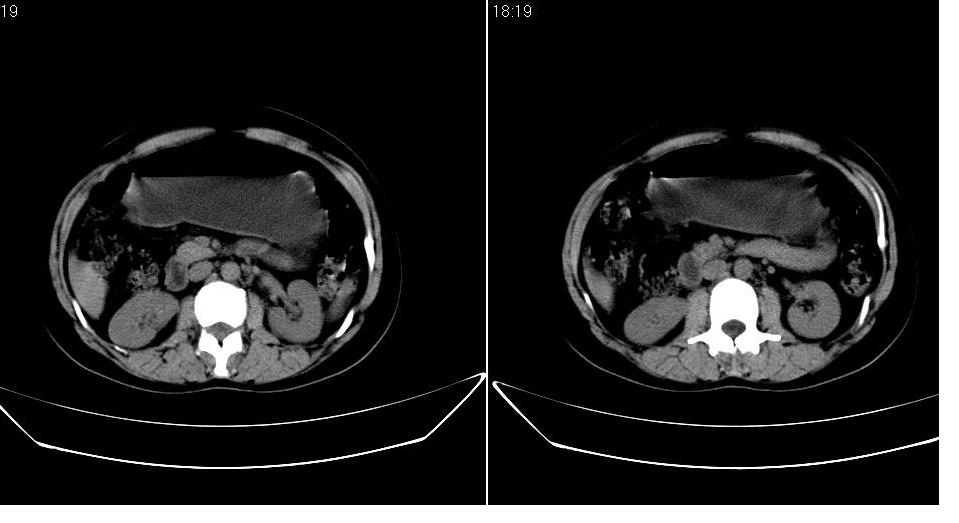

女 36岁,腹痛月余,b超提示肝左叶占位,腹水。

肝脏左叶明显增大,各叶比例失调,左叶实质内不均匀低密度影,似乎有肝内胆管的扩张,没有增强实在不好判断,不知患者肝功能是否正常,我觉得象胆管细胞癌。

从这个平扫图像看,只能诊断肝左叶占位,具体性质没有增强扫描不能诊断,只能说肝左叶低密度影,建议增强扫描进一步检查。

1)考虑肝左叶肝癌;建议行进一步检查。2)肝硬化,脾稍大。3)双侧少量胸腔积液。

支持!且患者肝门部有淋巴结转移。

肝脏左叶明显增大,且左叶实质内不均匀低密度影。考虑左叶占位??建议增强后再讨论。